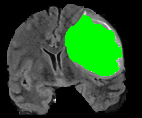

V-C Non-Registered MRI Segmentation Experiments

To demonstrate the robustness of the superpatch structure and the proposed framework, we apply SPM to brain tumor segmentation on multi-modal non-registered Magnetic Resonance Images (MRI). Classical patch-based and multi-atlas structure segmentation methods are based on registered subjects. Consequently, they cannot be efficiently applied in this non-registered context, due to the substantial variation in tumor shape and locations. Superpixels enable to better capture the tumor geometry, thus increasing the segmentation accuracy. Superpixel and supervoxel-based approaches have been applied to tumor segmentation [54]. However, in this work, the neighborhood is not considered and the ANN search is exhaustive, and computed on a large multi-modal histogram descriptor, leading to prohibitive computational time.

SPM can be efficiently applied to tumor segmentation since it quickly finds good correspondences without image registration, and uses the superpixel neighborhood to improve the matching. In this application, the segmentation is computed from a superpixel decomposition [1], then each region (tumor or background) is labeled with SPM.

We present results obtained on the MICCAI multi-modal Brain Tumor Segmentation (BRATS) dataset [49]. This challenging dataset contains real and simulated patient data, with overall poor resolution and large variation of tumor shape and position. For both types, high grade (HG) and low grade (LG) tumors are provided with four modalities: T1, contrast enhanced T1 (T1C), T2, and FLAIR. Overall, there are 20 and 10 real patient data with respectively HG and LG tumors, and 25 images for both HG and LG simulated tumor data. We use the same SPM parameters as in Section V-B, taking a multi-modal histogram, containing the levels of gray intensity on all MRI modalities as descriptor for superpatch matching, and performing the regularization (8) at the pixel scale to compare with pixel-wise ground truths. Each subject is segmented by the remaining of its type in a leave-one-out procedure.

In Fig. 12, we show several tumor segmentation results for all data types.

In Table II, we compare results obtained using different descriptor structures:

patch-based [48], superpixel-based [54],

and superpatch-based (= pixels).

We use the Dice coefficient [55] as evaluation metric,

measuring the overlap between the automatically segmented structure and the ground truth.

The superpixel-based approach

appears very limited since it fails at capturing the tumor context and their location in other images.

Regular patches are also limited in this context, due to the variations in the structure shapes.

Superpatches provide a robust descriptor, since they follow image intensities and capture the superpixel neighborhood,

leading to more accurate segmentation.

These experiments demonstrate that superpatches within the SPM framework provide fast and accurate segmentation results

even on non-registered multi-modal images with poor resolution.